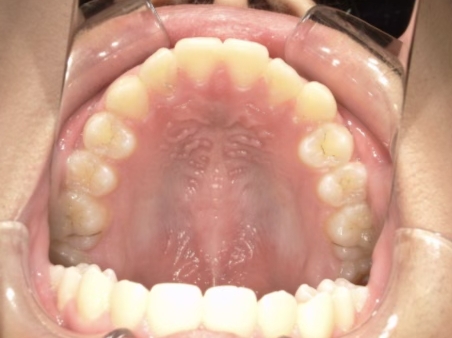

| カウンセリング・診断結果 | 前歯の生え変わり時期に来院されました。(写真①) 乳歯列期に受け口の既往があり切端咬合になりそうなため、受け口に対する矯正治療の考え方と対処法、当院のコンセプトを説明したところ治療を希望されたので診断を行いました。 診断の結果、上顎骨に対し下顎骨が長く、骨格的な構造も下顎突出型反対咬合(下顎骨が適切な位置よりも前に出ているタイプの受け口)と分かりました。 顔立ちは、中顔面が引っ込んだように見えるコンケーブに移行中です。 機能的な問題として低位舌があるため受け口の悪化が考えられることも説明し、以下の治療を提案しました。 |

| 行ったご提案・診断内容 | 成長期に行う治療と咬合治療をご提案 成長期受け口用モノブロック装置(筋機能的装置)を*MFTと併行して先行し、小学2年生以降で、拡大・前歯の調整へ移行し、咬合治療は受け口悪化予防と咬合の構築効果がある咬合治療用モノブロック装置(筋機能的咬合誘導装置)へ移行する提案をしました。 成長期治療(成長時期にお口の環境を整える治療) 咬合治療 経過観察 |